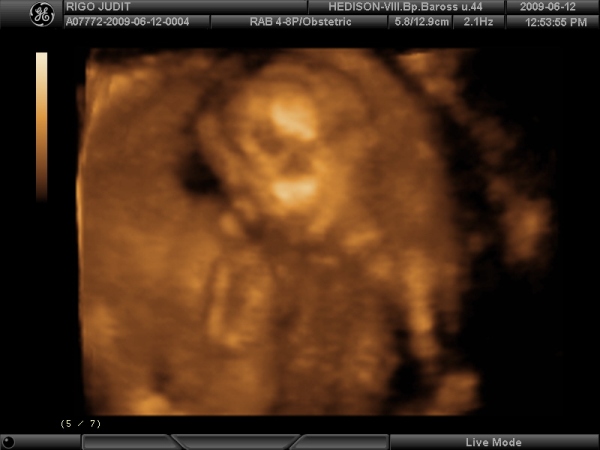

Szóval elég sok minden miatt "jó lenne" ha kislány lenne, de tényleg mindennél fontosabb az egészsége, és hogy boldogok legyünk mindannyian. Remélem így lesz. De azért csak álmodozhat az ember. Pár hét múlva már erre sem lesz lehetősem, ha végre kiderül mit rejt a lábaköze!